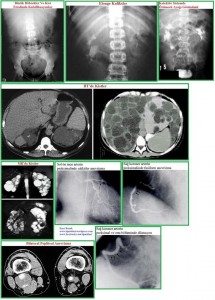

Renal bulgular: böbrek kistleri, nefrolitiazis, üriner sistem infeksiyonu, hipertansiyon, böbrek yetersizliği. Ekstrarenal bulgular: pankreas kistleri, kolon divertikülleri, herniler, dalak kistleri, intrakranial anevrizmalar, mitral kapak prolapsusu, karaciğer kistleri.

Ekstrarenal bulgular: Kistik bulgular: karaciğer (en sık karşılaşılan ekstrarenal bulgudur, karaciğer fonksiyon bozukluğuna yol açmaz), pankreas, dalak, seminal vezikül, araknoid. Nonkistik Bulgular: mitral kapak prolapsusu, anevrizmalar, kolon divertikülleri, herniler (inguinal, insizyonel, paraumbilikal).

İntrakranial anevrizmalar: Hastaların %5-10’unda görülür. Ailevi olma özelliği vardır. Rüptür riski, anevrizmanın çapı ile orantılıdır. Rutin tarama gereksizdir. Aile hikayesi pozitif olanlar veya daha önceden anevrizma rüptürü olanlar taranmalıdır. Tarama, magnetik rezonans anjiyografi ile yapılmalıdır. Anevrizma yoksa, tarama 5 yılda bir tekrarlanmalıdır. Çapı <6 mm olan anevrizmaların 2 yılda bir kontrolü gereklidir. Çapı >6 mm olan anevrizmalara cerrahi tedavi gereklidir.

Tanı: Pozitif aile hikayesi önemlidir. Radyolojik incelemeler: 1-Ultrasonografi: aile hikayesi pozitif olan bir kişide ultrasonografik tanı kriterleri; <30 yaşta ünilateral veya bilateral 2 kist olması, 30-59 yaşta bilateral 2’şer kist olması, >60 yaşta bilateral 4’er kist olması. 2-Bilgisayarlı tomografi. 3-Magnetik rezonans görüntüleme. Gen bağlantı analizi.

Görüntüleme yöntemleri: Direkt grafi, intravenöz ürografi, ultrasonografi, bilgisayarlı tomografi, manyetik rezonans, anjiografi, nükleer yöntemler, retrograt piyelografi, intravenöz piyelografi, ekskretuvar ürografi.